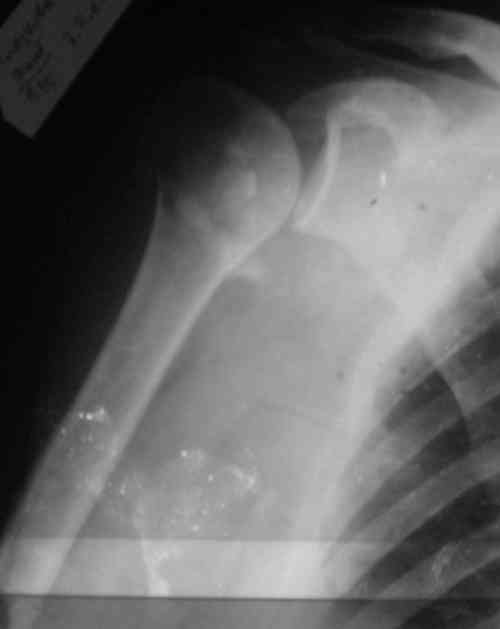

Снимки на 1-е сутки после репозиции и на 8- сутки после репозиции.

Пожалуйста

С ув. Sergey A. Melashenko, г. Запорожье

На 20-е сутки снял гипс, одел фиксирующюю

ортопедическую повязку. Вот контроль. Как видно, стояние хорошее, уже формируется костный мозоль.

Думаю еще недели 3 продолжать фиксацию.